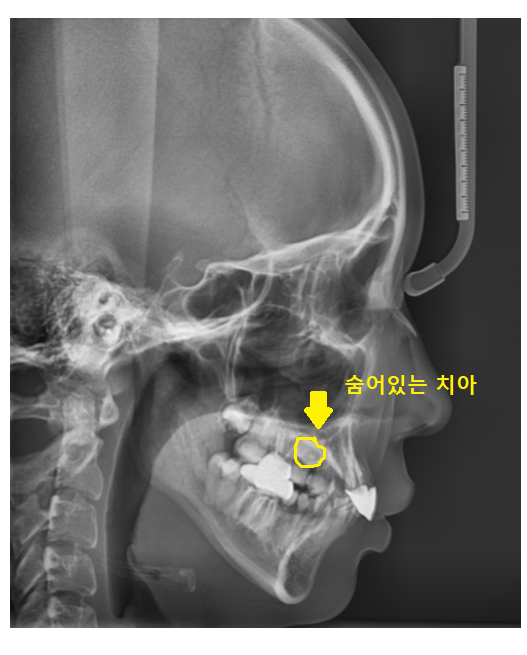

23.07.01

교정 진단을 위해 촬영한 사진에서도

숨어있는 매복치 보이시죠~?

교정 치료 위해서는 치아를 발치해야하는데

숨어있다보니 잇몸을 열고

수술에 준하는 교정 발치 진행하여야합니다.